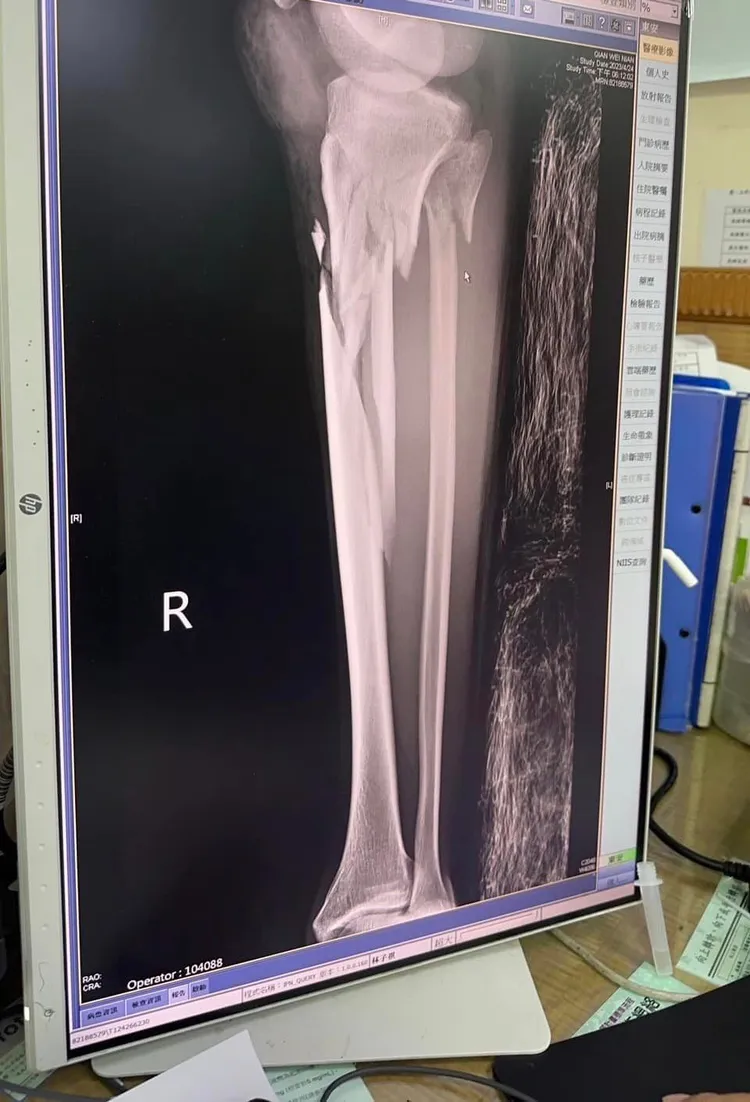

她表示,親弟弟騎機車直行,遭酒駕汽車對撞,弟弟雙腿開放性,粉碎性骨折,骨盆裂了,質疑是不是要等到大法官,還是執法人員的家人身上,才會感同深受?法令才會修改嚴懲?「我真的不知道要罵什麼了,真的…」。